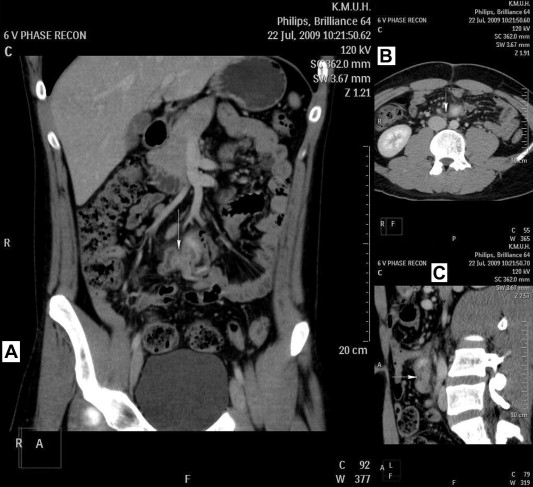

A man 18 years of age came to our outpatient department and was hospitalized because of tarry stool. There were no other associated gastrointestinal symptoms and signs, such as nausea, vomiting, epigastralgia, abdominal pain, or diarrhea. A series of tests revealed the following: hemoglobin level of 8.9 mg/dL; abdominal computed tomography (CT) scan showed a Meckel diverticulum with infection and one polypoid lesion within the diverticulum (Fig. 1); and echnetium-99m–labeled ectopic gastric mucosal scintigraphy showed a focal radiotracer uptake in the middle abdomen (at the level of aortic bifurcation) since 15-minute image and increased radioactivity with time as gastric mucosa pattern, synchronized.

Fistula (arrow) of Meckel diverticulum and apex of appendix; (A) coronal view; ...

Fistula (arrow) of Meckel diverticulum and apex of appendix; (A) coronal view; (B) axial view; and (C) sagittal view.